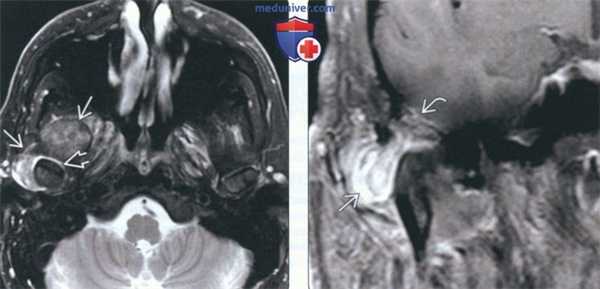

(Слева) На аксиальной МРТ (Т2 ВИ FS) у пациента с болезнью накопления КПФД вокруг компонентов правого ВНЧС визуализируется неоднородное объемное образование с преимущественно гипоинтенсивным сигналом. Обратите внимание на гиперинтенсивную жидкость в суставном пространстве вокруг мыщелка нижней челюсти.

(Справа) На корональной MPT (Т1 ВИ С+) у этого же пациента определяется контрастное усиление объемного образования в нижних наружных отделах. Обратите внимание на дефект крыши суставной ямки и легкое контрастирование твердой мозговой оболочки. Интракраниальное распространение отсутствует.

(Слева) При МРТ Т2ВИ FS в аксиальной проекции у пациента с болезнью депонирования кальция пирофосфата возле правою височно-нижнечелюстного сустава визуализируется патологический участок с неоднородным, преимущественно гипоинтенсивным сигналом. Наблюдается жидкость в суставном пространстве вокруг головки мыщелка нижней челюсти.

(Справа) При МРТ Т1ВИ FS с КУ в корональной проекции снизу и снаружи визуализируется объемное образование, накапливающее контраст. Отмечается дефект кости, формирующей суставную ямку, и легкое контрастное усиление твердой мозговой оболочки; но явные признаки распространения процесса в полость черепа отсутствуют.